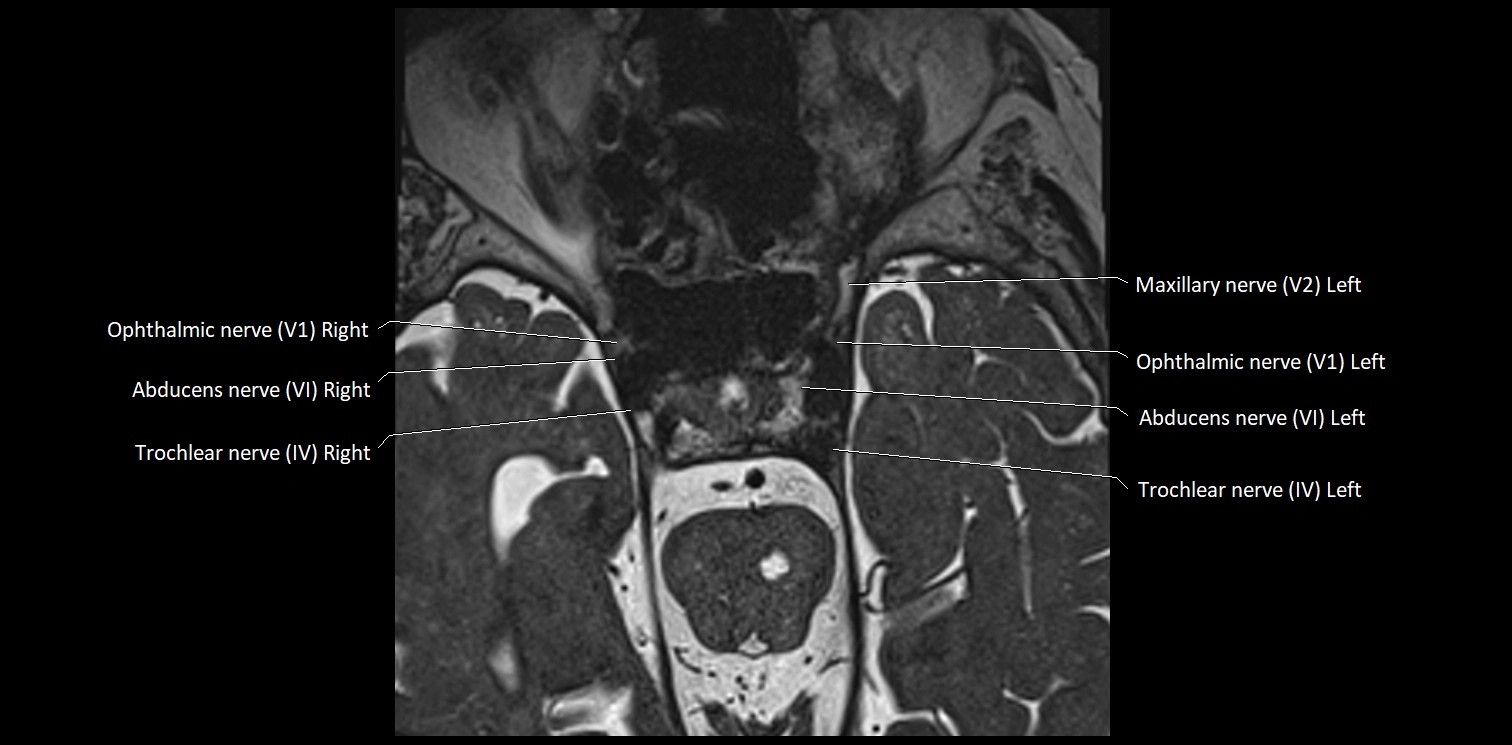

MRI Appearance

• The abducens nerve is a small, thin, linear structure

• Best visualized on high-resolution T2-weighted 3D MRI sequences (e.g., FIESTA or CISS)

• Seen as a hypointense (dark) line running from the brainstem at the pontomedullary junction, traversing the prepontine cistern, and entering Dorello’s canal under the petrosphenoidal ligament, then into the cavernous sinus, and finally the orbit

• May be challenging to visualize in standard MRI due to its small size

• Pathology may be inferred by absence, displacement, or enhancement of the nerve

MRI images

image